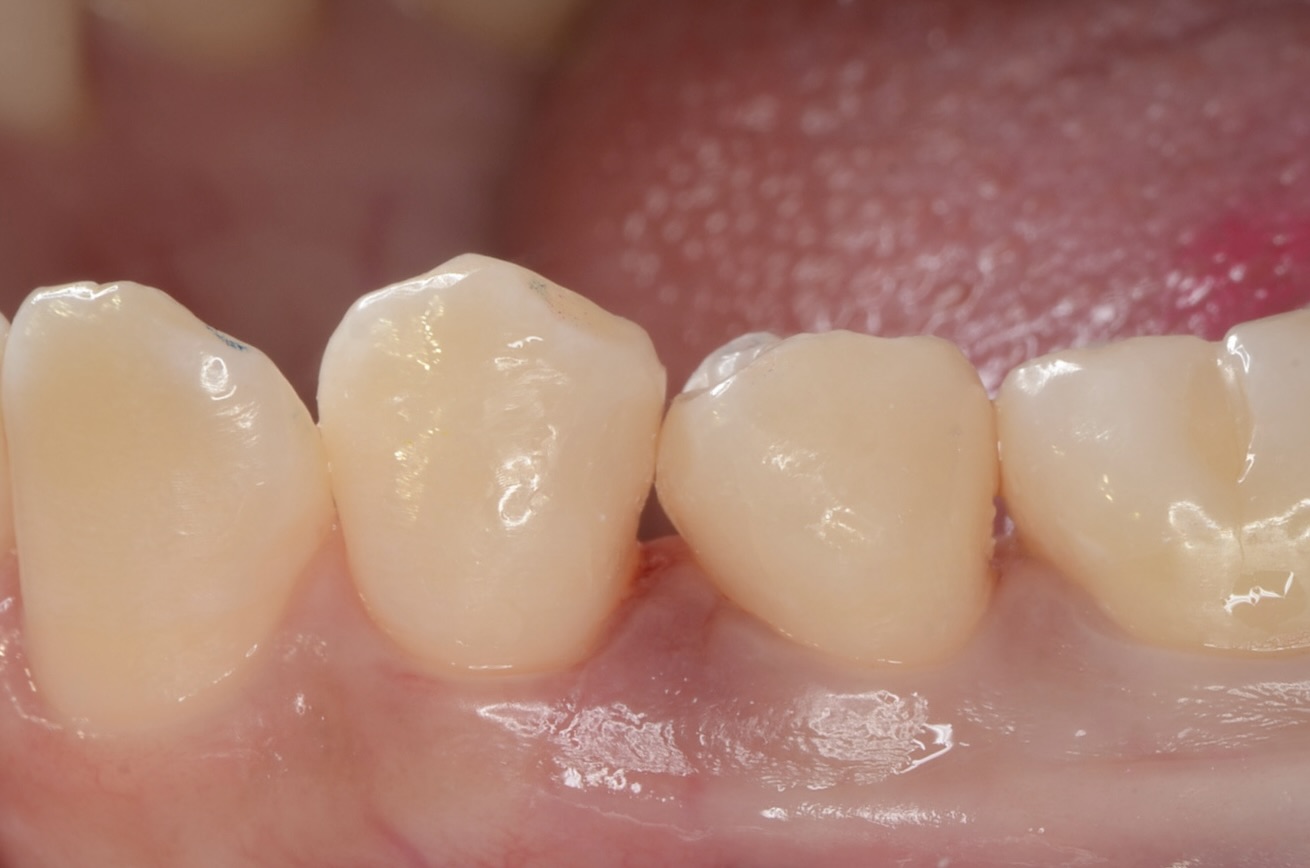

After

このように歯並びが若干乱れている場合の、歯と歯の間にできた虫歯治療は意外と難易度が高いです。しかしセパレーターを使って歯間離開させ、フロワブルレジンの表面張力を利用して充填すれば、滑らかで、引っ掛かりのない歯の形態を再現できます。

ダイレクトボンディングを検討されている方は、こちらのページをご覧ください。